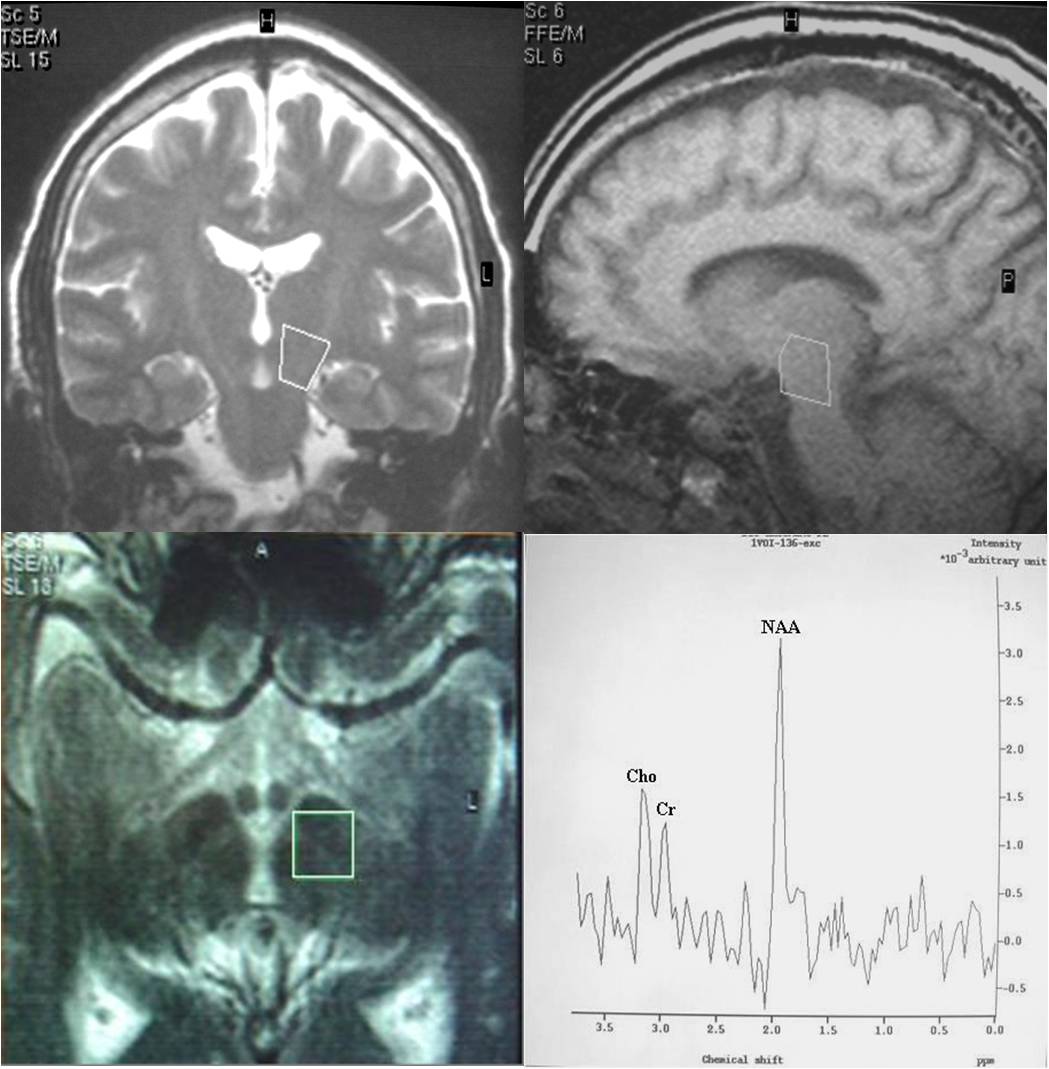

Objective: To use 1.5T 1H-MRS as a research tool in vivo and demonstrate the feasibility of obtaining long-echo 1H MR spectra in small volumes like substantia nigra (SN) and medulla oblongata (MO) in healthy volunteers and patients with Parkinson's disease (PD) and observe the clinical correlations.

Subjects and Methods: Twenty patients of the idiopathic Parkinson’s disease (IPD) were recruited from the Out Patient Department of Neurology. Additionally, 14 age-matched healthy subjects were taken as controls group. After baseline evaluation, the patients satisfying inclusion and exclusion criteria underwent 1H-MRS study. All MR examinations were performed on a 1.5 T system (Philips Gyroscan Intera, Netherlands) using a standard quadrature head coil.

Results: We succeeded to achieve 74.19% and 77.42% of spectra from MO and SN of both PD and control groups. MO showed slightly weak negative result to total UPDRS and UPDRS- II, but no significant correlation was found between metabolites and clinical indexes in MO. The result also showed no significant correlations between H&Y scale and metabolites in MO and SN of PD patients. But there was a significant correlation between H&Y, NAA/Cr and Cho/Cr in SN.